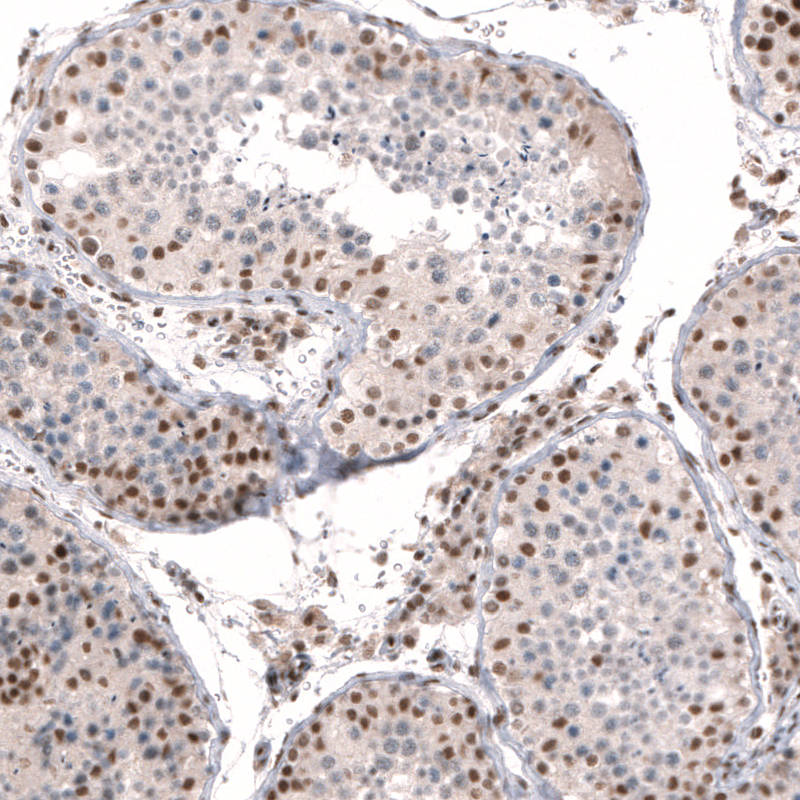

Immunohistochemistry analysis in human testis and liver tissues using HPA044341 antibody. Corresponding CIC RNA-seq data are presented for the same tissues.